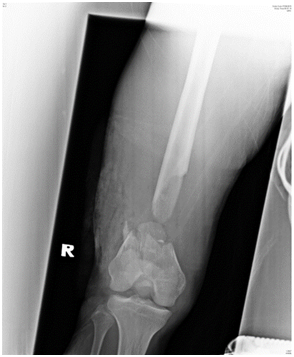

The patient was allowed active mobilization of the knee joint after surgery but weight bearing on the injured limb was strictly not allowed. The patient was allowed partial weight bear and full weight bear at 4 and 6 months respectively. The fracture achieved radiological union at 6 months after internal fixation and bone grafting (Figure 3A & 3B). Patient was able to ambulate independently without aid. Right lower limb however was shorter by 2cm but patient did not have any functional complain and this can be equalized with a shoe lift. Right thigh muscles were atrophic. Passive range of motion of the right knee was 0 to 130 degrees while active range of motion was 10 to 120 degrees. Ankle joint was stable. Fibular graft donor site healed with no complication.

Figure 3a Figure 3A(Right) Radiograph of the right femur, AP view, six months after surgery showing fracture site union with incorporation of the fibula graft.

Figure 3b (Left) Radiograph of the right femur, lateral view, six months after surgery showing fracture site union with incorporation of the fibula graft